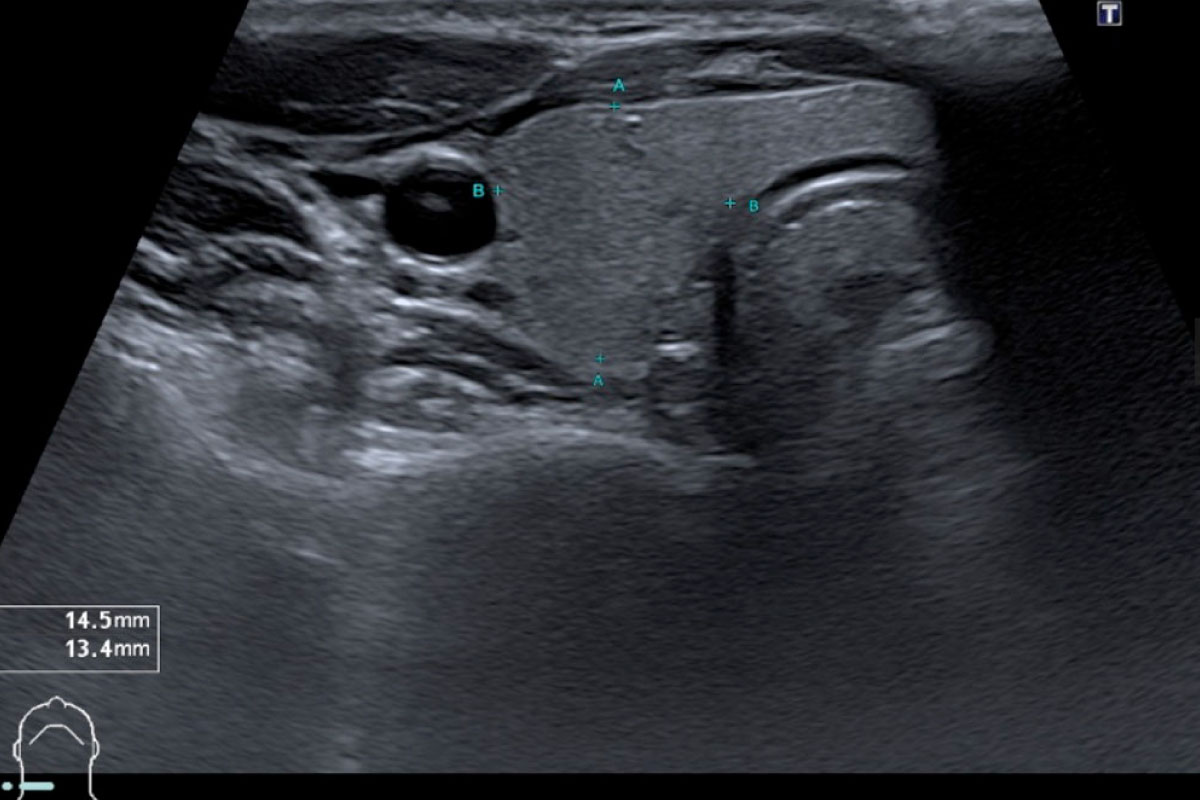

Sonographie

Ultraschall von Bauchorganen

Die Ultraschalluntersuchung ist ein schonendes und schmerzfreies Verfahren, mit dem man alle Organe des Bauchraumes darstellen kann. Hierzu gehören:

- Leber,

- Gallenblase und die Gallenwege,

- Bauchspeicheldrüse,

- Nieren

- und Milz.

Zusätzlich kann man auch den Darm sowie die großen Blutgefäße des Bauchraumes hiermit untersuchen.

Bei der Untersuchung wird ein Ultraschallkopf, welcher Ultraschallwellen aussendet auf die Haut aufgelegt.

Die Ultraschallwellen werden von den verschiedenen Geweben und Strukturen unterschiedlich reflektiert, wodurch ein Bild entsteht welches die Beurteilung der Organe ermöglicht.

Die Sonographie kann dabei sowohl zur Abklärung akut auftretender Beschwerden benutzt werden als auch zur Verlaufsbeurteilung bestehender Erkrankungen. Die Untersuchung wird im Liegen durchgeführt und dauert in der Regel nur ein paar Minuten.

Zur differentialdiagnostischen Abklärung von Bauchschmerzen kann auch die Ultraschalluntersuchung des Darmes ein wichtiger Baustein sein.

Mit Hilfe von modernen hochauflösenden Ultraschallsonden kann man präzise den Dünn- und Dickdarm darstellen, um so Erkrankungen wie z. B. eine Appendizitis, eine Divertikulitis oder chronisch-entzündliche Darmerkrankungen festzustellen.

Insbesondere bei den chronisch-entzündlichen Darmerkrankungen Morbus Crohn und Colitis ulcerosa ist die Darmsonographie eine sehr gute Methode, um den Krankheitsverlauf und den Therapieerfolg zu überwachen.

Ultraschall der Schilddrüse

Die Untersuchung der Schilddrüse mittels Ultraschall wird häufig bei Symptomen der Schilddrüsenüber- oder -unterfunktion durchgeführt oder wenn in der Routinelabordiagnostik veränderte Blutkonzentrationen von Schilddrüsenhormonen aufgefallen sind.

Bei der Schilddrüsen-Sonographie können die Größe der Schilddrüse, die Struktur des Organs (beispielsweise Knoten) und die umliegenden Strukturen wie Lymphknoten und Blutgefäße beurteilt werden.